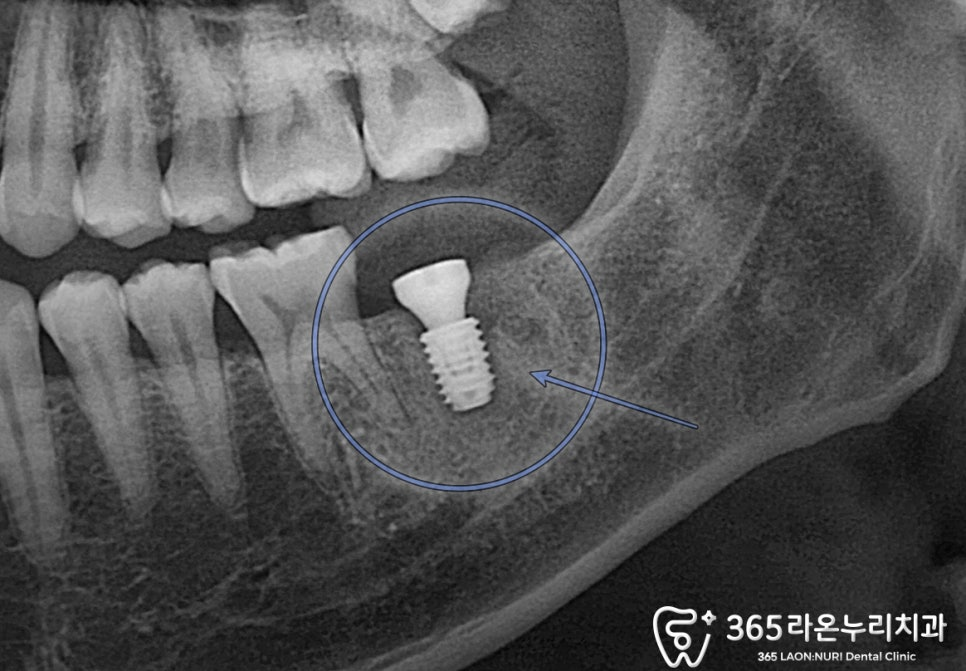

『 Panorama X-ray 』

먼저 서정리역 치과 에서

파노라마 엑스레이 촬영본을 함께 보겠습니다.

2024.12.21

왼쪽 아 어금니 뿌리를 가만히 들여다보면

시커멓게 변한 부위를 볼 수 있을 겁니다.

염증이 나타난 것을 보여주는데요.

세균 감염에 의하여 나타난 결과입니다.

이미 커질만큼 커져버린 감염 부위는

치료를 진행한다 하더라도,

예후가 좋지 않았습니다.

차라리 발치 하는 게

남은 이를 보존하는데 도움을 주는데요.

2025.1.25

implant를 식립한 후에는,

일정 기간 동안 치유기간을 가지게 됩니다.